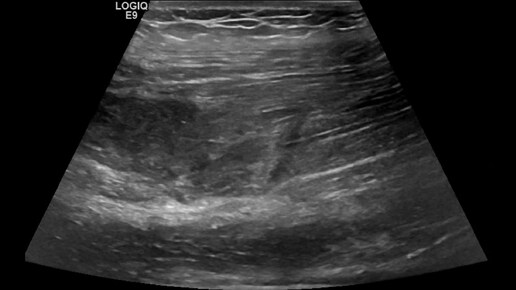

Видео к статье "Межмышечная гематома бедра"https://dzen.ru/a/Z8xoM3I0bnbKMU5K

Ультразвуковые находки от врача УЗД Зорина Я.П.